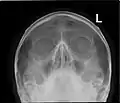

![]() Paranasal sinuses seen in a frontal view | |

Paranasal sinuses radiograph (occipitofrontal)

Paranasal sinuses radiograph (occipitomental)